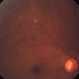

- pan-retinal photocoagulation (PRP), neovascularization (NV)

- 5 months s/p, PRP, Pt. GL.